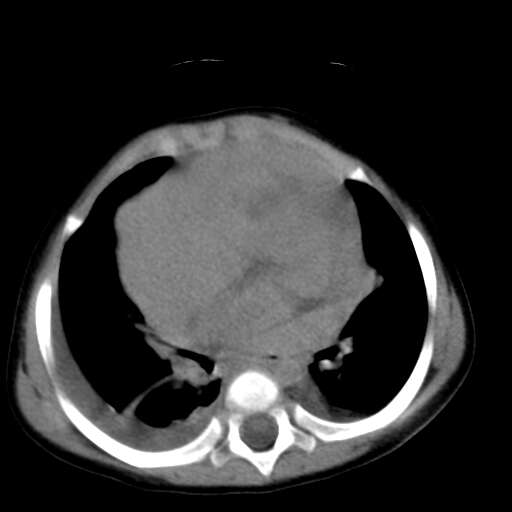

患儿1y,女,因支肺炎经dr检查发现前上纵膈占位而行ct检查,肿块与心血管脂肪间隙模糊消失,可见斑点状钙化,未见脂肪成分,双侧胸水,考虑侵袭性胸腺瘤

1、定位:前上纵隔,血管及头臂干前方,胸腺部位。

2、巨大实性肿块,其内见小片状低密度灶和少许点状钙化。

3、双侧胸腔积液,提示肿瘤恶性可能。

4、双肺下也背侧肺间质水肿改变。